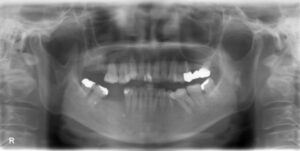

上下大臼歯2本欠損症例

BEFORE AFTER 29歳男性/上下顎2本欠損/インプラント埋込手術 【治療内容】 左上第二大臼歯と右下第二大臼歯…